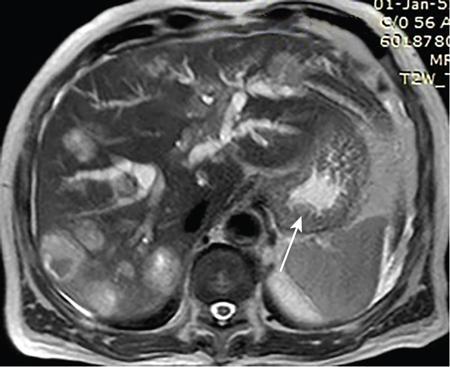

High-resolution computed tomography (HRCT) lung (axial and coronal reformatted images) of a 32-year-old female patient shows a dilated patulous distal oesophagus and gastro-oesophageal junction (arrow) and features of Usual interstitial pneumonia (UIP) pattern of interstitial lung disease.

Image

Fig. 7.4.3.4 HRCT images showing dilated patulous GE junction and UIP pattern of interstitial lung disease.